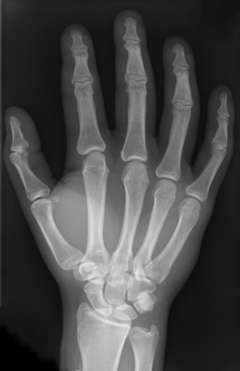

X-ray of the bones in the hand

The intermetacarpal joints are in the hand formed between the metacarpal bones. The bases of the second, third, fourth and fifth metacarpal bones articulate with one another by small surfaces covered with cartilage. The metacarpal bones are connected together by dorsal, palmar, and interosseous ligaments.